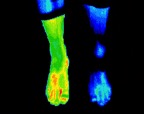

3- Stress fracture right ankle.jp2

Stress fracture right ankle

4- Poorly healed left ankle fracture.jp2

Poorly healed left ankle fracture

5- Left ankle fracture.jp2

Left ankle fracture